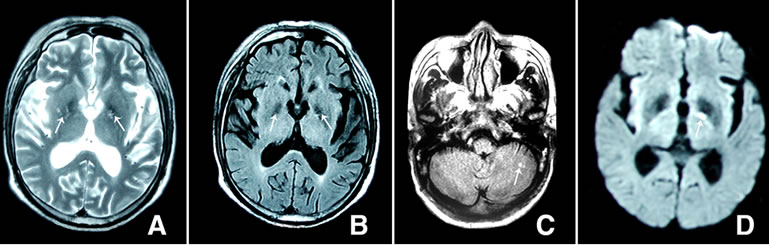

Figure 1. Brain magnetic resonance images, obtained on the 15 day. (A) T2-weighted image shows low signal intensities in the putamen and focal high signal intensity in the putamen (arrow); (B) The T1-weigted image shows low signal intensity in the putamen (arrow); (C) The Flair image shows high signal intensity in the left cerebellar (arrow); (D) The diffusion-weighted images shows signal intensity in the left putamen (arrow).

On the other hand, hyperglycemia can disrupt the blood-brain barrier and produce a global decrease in regional cerebral blood flow [11,12], even lead to neuronal death [13,14]. Experimental data demonstrated that high glucose causes activation of several proteins involved in apoptotic cell death [15]. Some authors suggest that insulin deficiency plays a compounding role to that of hyperglycemia in neuronal apoptosis underpinning primary diabetic encephalopathy [16]. Delayed ischemic hyperintensity on T1-Weighted images and selective neuronal death and gliosis in the putamen of rats after brief focal ischemia have been reported. Recently, an interesting finding has been put forward by Raghavendra S et al. [17] suggesting that focal neuronal loss occurs in bilateral striatal T2 hyperintensity in nonketotic hyperglycemia. However, our patient had hemichorea associated with diabetes mellitus with nonketotic hyperglycemia, and T2-weighted image and the DWI on the brain showed signal intensities in the putamen, and the T1-weigted image showed low signal intensities in the putamen, and the Flair image shows high signal intensity in the left cerebellum.